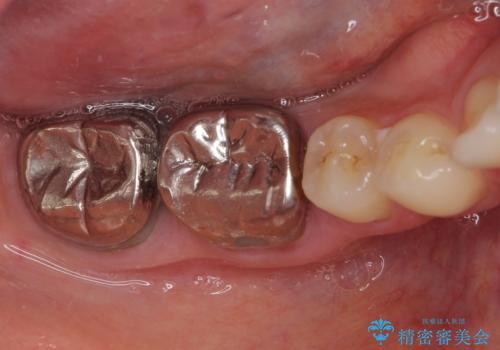

- 前歯の隙間と奥歯の目立つ銀歯を気にして来院された患者様です。

インビザラインにより下顎前歯の隙間を閉じるとともに、奥歯の咬み合わせを改善させることとしました。

矯正治療後には、銀歯のクラウンをセラミッククラウンへ替える補綴治療を行うこととしました。